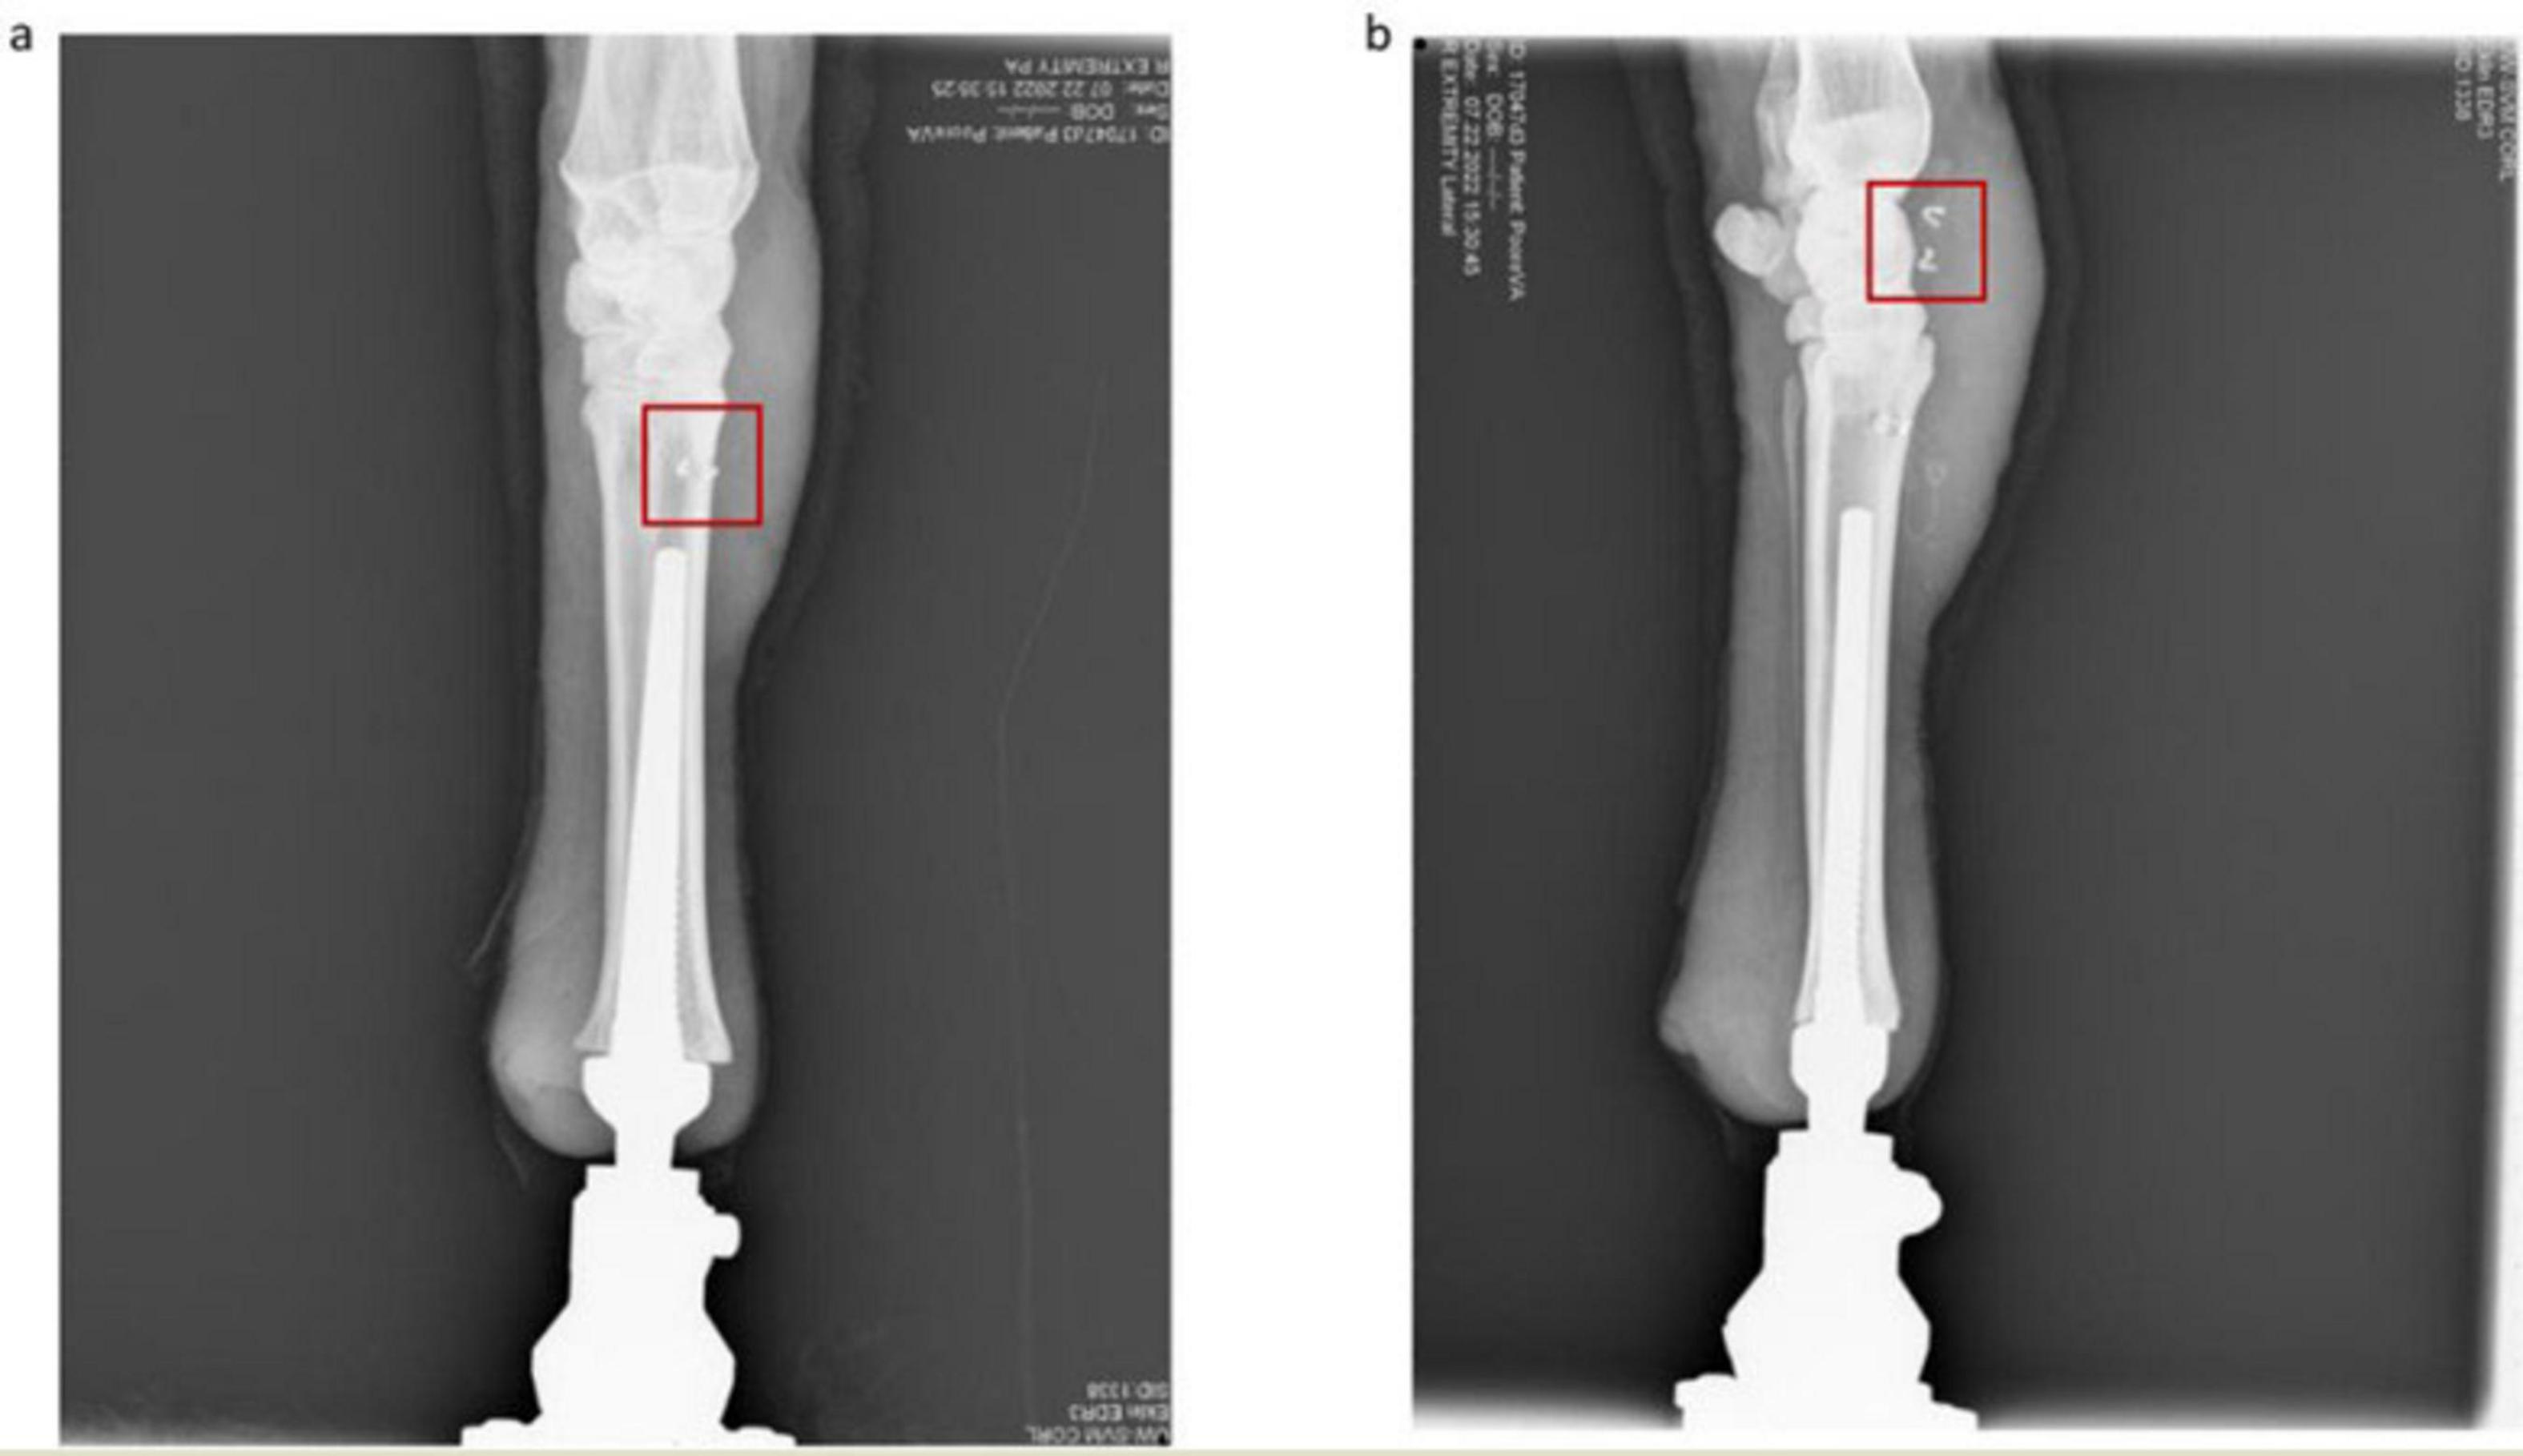

FIGURE 5

(a) Anterior view of osseointegrated ovine thoracic limb for Sheep A. The osseointegrated implant is nested within the reamed medullary canal and the intramedullary electrodes are outlined in red. (b) Lateral view of osseointegrated ovine thoracic limb. The recording electrodes proximal to the corticotomy are outlined in red.

Postoperation, sheep were closely observed to ensure proper behavioral and physical recovery following implantation and osseointegration. Accompanying our qualitative observations, radiographs were taken of the recovering forelimb to visualize the repair process and validate the successful placement of our cuff electrodes. Four weeks post-implantation, Sheep A was fully weight-bearing and freely ambulating on the prosthetic limb; her behavior was recorded as bright, alert, and responsive. Successful osseointegration was qualitatively inferred from pain free ambulation with weight-bearing on the prosthetic and the absence of appreciable changes in implant position from week to week.

At approximately 9 weeks post-operation, lameness appeared in Sheep A. Following immediate consultation with the veterinary orthopedic surgeon, the primary diagnosis of osteomyelitis was made via radiological imaging (Figure 8A, yellow arrow), and the decision was made to immediately euthanize based on recommendation. A full necropsy was performed by a board-certified veterinary pathologist and soft tissue, bone, and implant material samples were all taken from several areas and both aerobic and non-aerobic cultures came back negative. Complete blood count (CBC) was unremarkable. Histology showed increased bone remodeling. The bone lysis seen on radiographs was not due to an infection, but possible osteonecrosis or avascular ischemia. Further studies are needed to determine the cause.

FIGURE 8

(A) Radiological imaging of Sheep A from 0 weeks post-op (WPO) to 8 WPO (B) radiological imaging of Sheep B from 0 WPO to 1 year and 3 months post-op.

We demonstrate the feasibility of a wireless Ovine Osseointegrated Neural Interface (ONI) model, supported by radiological evidence from Sheep A and Sheep B (Figure 8B), as well as electrophysiological evidence collected exclusively from Sheep A. The model is the product of osseointegration, a refined surgical methodology, and a dual capsule implantable neural interface capable of wirelessly transmitting neural recording data to an external DAQ system. The wireless interface functioned reliably over the study period, illustrated by the presence of synchronization pulses 8 weeks post-surgery. Despite this, an idiopathic and progressive osteolytic lesion required premature euthanasia prior to telemetric failure to prevent untreatable pain and discomfort. Future goals of this model involve additional design optimizations such as advancing to a closed loop system to enhance interface functionality and expanding to a truly bidirectional design.